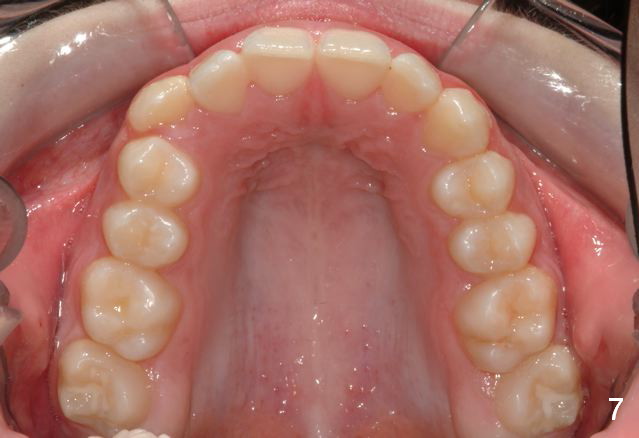

Unilateral Class II Malocclusion

The upper dental midline deviates to the left (Fig.2,4). Facial profile is normal (Fig.3). The right molar relationship is Class II (Fig.5), while the left one is normal or slightly Class III (Fig.6). How to treat?